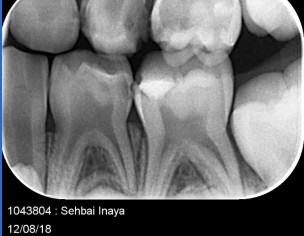

My daughter is 7 and hav deep cavity I took her to dentist one said she need 1 extraction and when I went to pediatric dentist she said she needs 4 extractions which she is going to do altogether same day I am attaching her xrays can any dentist plz advise after looking at the xrays thanks

Her both upper D are definitely for extraction and for her E need to evaluate clinically as well there might get b some Endodontic treatment and space maintainers afterwards